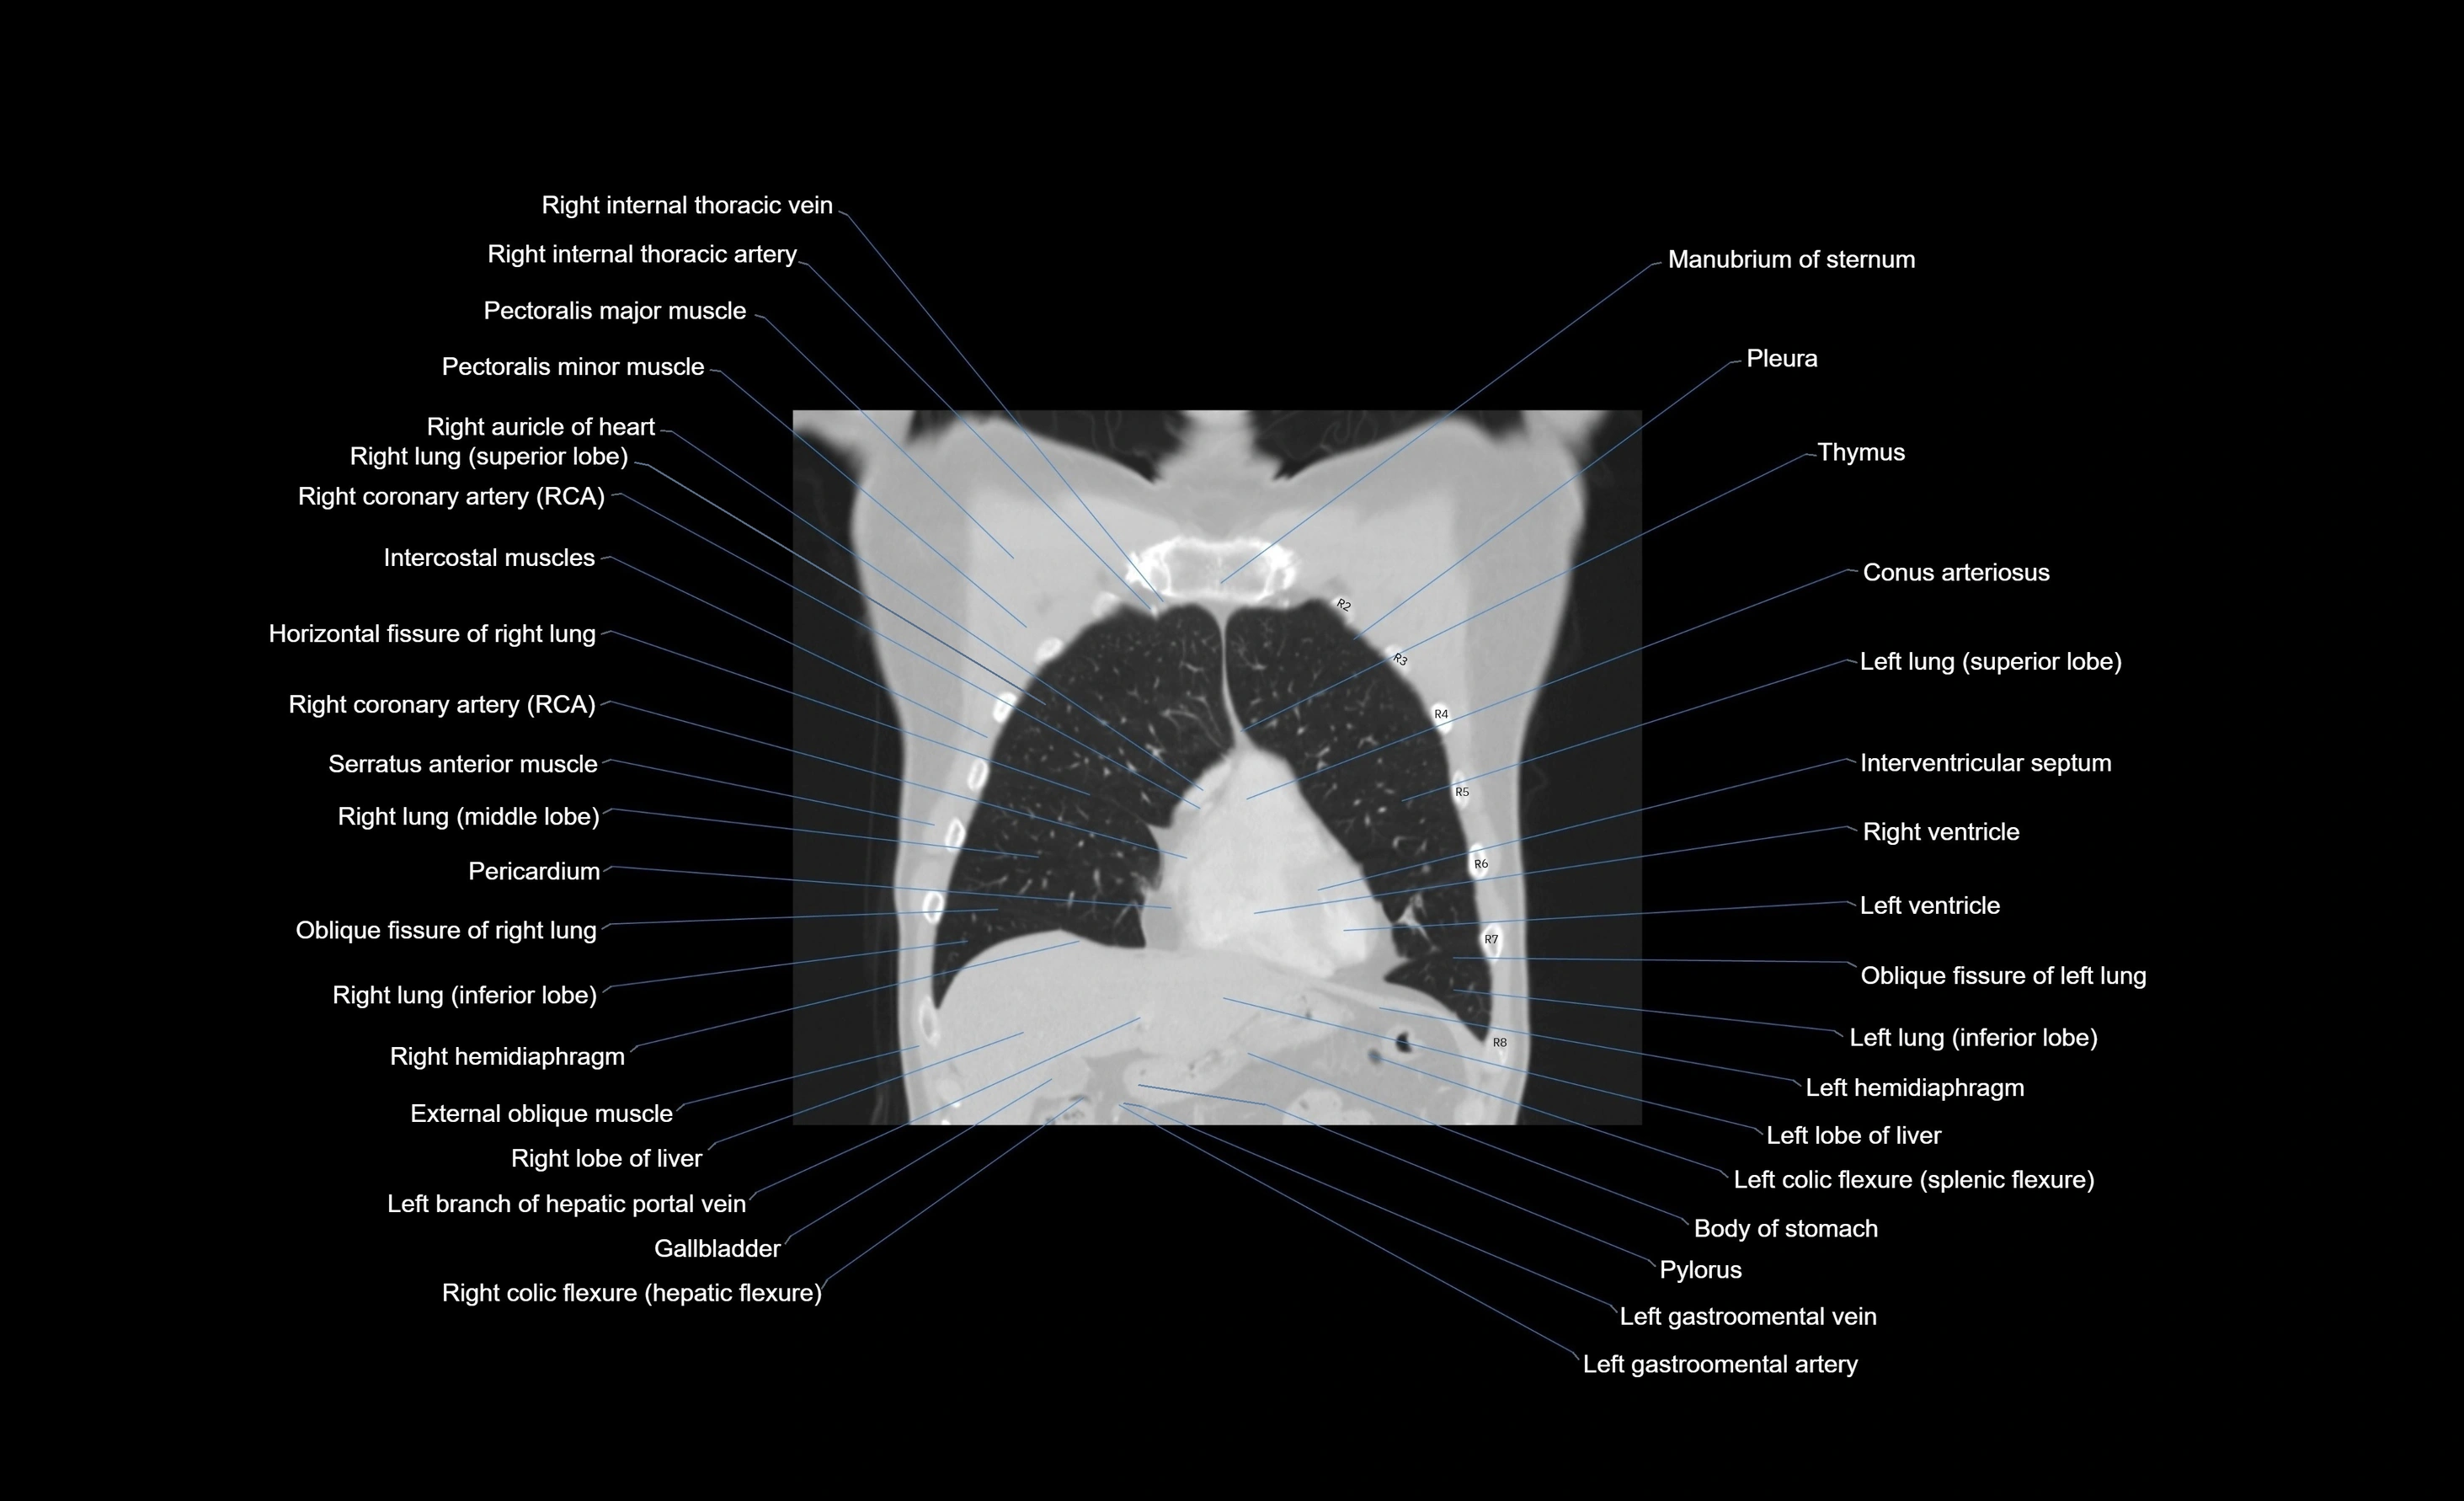

- Conus arteriosus

- Horizontal fissure of right lung

- Intercostal muscles

- Interventricular Septum

- Left hemidiaphragm

- Left lung (inferior lobe)

- Oblique fissure of right lung

- Pectoralis major muscle

- Pectoralis minor muscle

- Pericardium

- Pleura

- Right coronary artery (RCA)

- Right hemidiaphragm

- Right internal thoracic artery

- Right internal thoracic veins

- Right lobe of liver

- Right lung (middle lobe)

- Right lung (superior lobe)

- Right ventricle